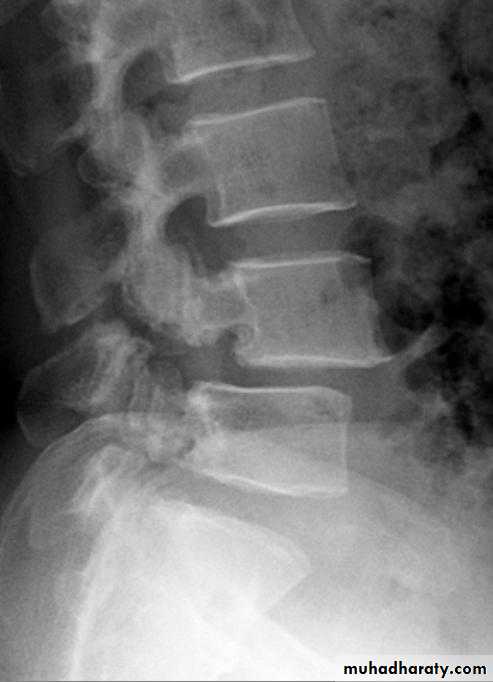

X-Rays:

Flattening of the disc space and marginal osteophyte formation appear later.• CHRONIC INTERVERTEBRAL DISC DEGENERATION

Bulging of the annulus fibrosus in both sagittal and axial projections and diminished thickness and reduced signal intensity (dehydration) of the degenerating disc.

Imaging:X-rays will show features of disc degeneration or spondylolisthesis. Measurement of the spinal canal can be carried out on CT and MRI.